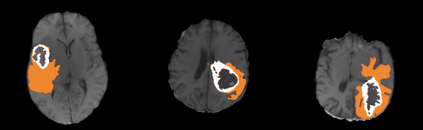

Transformer, the latest technological advance of deep learning, has gained prevalence in natural language processing or computer vision. Since medical imaging bear some resemblance to computer vision, it is natural to inquire about the status quo of Transformers in medical imaging and ask the question: can the Transformer models transform medical imaging? In this paper, we attempt to make a response to the inquiry. After a brief introduction of the fundamentals of Transformers, especially in comparison with convolutional neural networks (CNNs), and highlighting key defining properties that characterize the Transformers, we offer a comprehensive review of the state-of-the-art Transformer-based approaches for medical imaging and exhibit current research progresses made in the areas of medical image segmentation, recognition, detection, registration, reconstruction, enhancement, etc. In particular, what distinguishes our review lies in its organization based on the Transformer's key defining properties, which are mostly derived from comparing the Transformer and CNN, and its type of architecture, which specifies the manner in which the Transformer and CNN are combined, all helping the readers to best understand the rationale behind the reviewed approaches. We conclude with discussions of future perspectives.